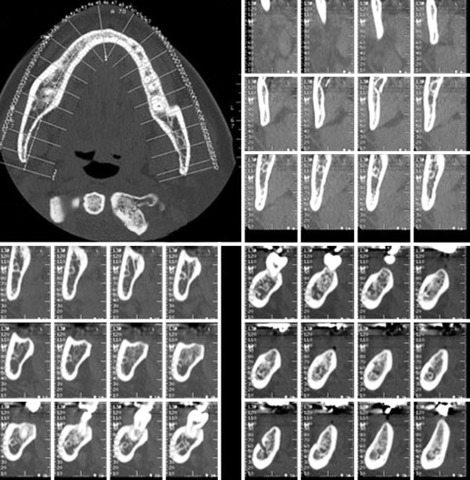

(TCHC –Tomógrafo Computerizado de Haz Cónico–, o CBCT –Cone Beam Computed Tomography, Europa (1997-1999)

Introducidas a raíz de los trabajos elaborados en el Proyecto Phidias